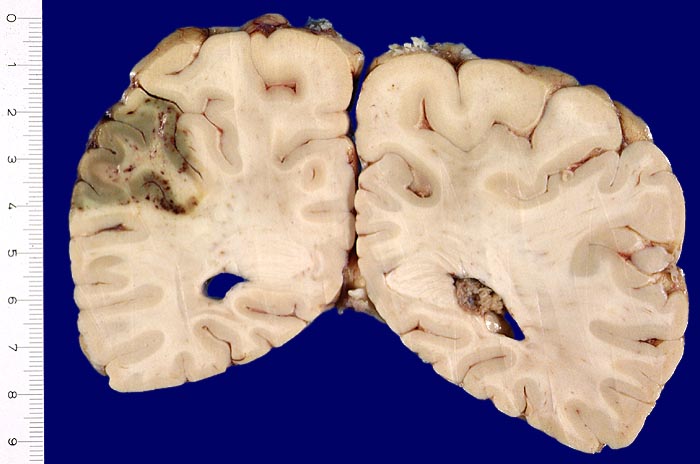

• Frische Nekrose und Demarkation (0-5 Tage): Makroskopisch nach 12 Stunden leichte Erhabenheit erkennbar (Ödem). Erweichung. Unscharfe Mark-Rindengrenze. Mikroskopisch eosinophile Degeneration der Neurone und ödematöser Randsaum.

• Resorption und Abräumung (ab 5. Tag, vorliegender Fall): Mit zunehmendem Alter des Infarktes wird das Gewebe weicher und zerfällt innerhalb einiger Wochen zerfliessend kleinzystisch (Kolliquationsnekrose). Mikroskopisch ab dem zweiten Tag Auftreten von Makrophagen im Randbereich. Durch Phagozytose von Myelinbruchstücken lipidhaltige Vakuolen im Zytoplasma der Makrophagen (=Fettkörnchenzellen). Nervenzellen im Randbereich der Nekrose können das Bild einer ischämischen Schädigung zeigen (Hypereosinophilie). Gefässproliferation. Perifokale Gliose.

• Organisation und Zystenbildung (ab 1-8 Wochen): Übergänge zum Stadium 2 sind fliessend. Vermehrung von Fettkörnchenzellen rund um proliferierte Kapillaren. Endstadium des anämischen Infarktes bildet ein zystischer Parenchymdefekt, im Gegensatz zu anderen Organen (Herz, Niere) findet kein narbiger Umbau statt. Die in der deutschsprachigen Literatur oft erwähnte "Hirnnarbe" bezieht sich auf die reaktive Gliose im Randbereich des Infarktes. Eine reaktive Gliose ist unspezifisch und findet sich in der Nachbarschaft verschiedener Läsionen (beispielsweise Blutungen, Tumoren, Abszesse etc.). Alte abgebaute Infarkte sollen makroskopisch von alten Kontusionsherden abgegrenzt werden. Diese befinden sich praktisch ausschliesslich in frontobasaler oder temporobasaler Lokalisation (> 1436), wo umschriebene Hirninfarkte nicht vorkommen.

• Links unten leptomeningeale Gefässe mit partiell rekanalisierten alten thromboembolischen Verschlüssen.

• Unscharfe Mark-Rindengrenze im Bereich der nekrotischen Rinde.

• Spongiotische Auflockerung der Hirnrinde (hellere Areale).